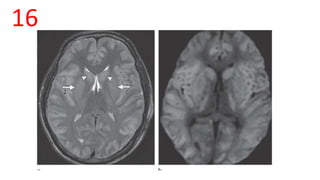

16

DD of b/l Basal Ganglia Hyperintensities in an adult

• • Hypoxic-Ischemic Injury – Near drowning, cardiac arrest,

• • Viral Encephlitis – West Nile, HSV, Japanese Encephalitis

• • Osmotic Demyelination Syndrome

• • Toxin exposure – CO poisoning - Globus pallidus involvement

• • Wilson disease

• • CJD

• • CVT

• • Metabolic – Hepatic, hypoglycemic Encephalopathy

17